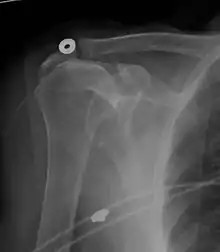

Диагностические методы, в зависимости от обстоятельств, включают в себя рентген, МРТ, МР-артрографию, артрографию с двойным контрастом и УЗИ. Хотя МР-артрография в настоящее время считается золотым стандартом, ультразвук может быть наиболее экономически эффективным.[30] Обычно разрыв не определяется рентгеном, хотя могут быть видны костные шпоры, которые могут задевать сухожилия вращательной манжеты.[31] Такие шпоры предполагают хроническое тяжёлое заболевание вращательной манжеты плеча. Артрография с двойным контрастированием включает инъекцию контрастного красителя в плечевой сустав для обнаружения утечки из поврежденной вращательной манжеты[32] и её качество зависит от опыта оператора. Наиболее распространённым диагностическим инструментом является магнитно-резонансная томография (МРТ), которая иногда может указать размер разрыва, а также его расположение в пределах сухожилия. Кроме того, МРТ позволяет с достаточной точностью обнаружить или исключить полный разрыв вращательной манжеты плечевого сустава, а также подходит для диагностики других патологий плечевого сустава.[33]

Рентгеновский снимок

Рентгеновская проекционная рентгенография не может напрямую выявить разрывы вращающей манжеты, «мягких тканей», и, следовательно, обычные рентгеновские лучи не могут исключить повреждение манжеты. Однако косвенные доказательства патологии можно увидеть в случаях, когда одно или несколько сухожилий подверглись дегенеративной кальцификации (кальцифицирующий тендинит). Головка плечевой кости может мигрировать вверх (высоко расположенная головка плечевой кости) вследствие разрыва подостной или комбинированной надостной и подостной мышцами.[44] Миграцию можно измерить расстоянием между: